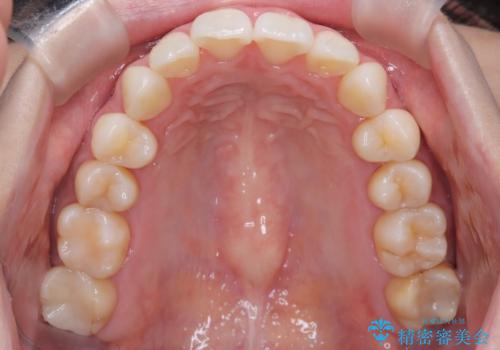

【インビザライン】前歯のねじれを治したい。

- 前歯の凸凹を主訴に来院されました。

スペースを作るために顎間ゴムを使用して、奥歯の遠心移動をおこない配列しました。

奥歯の遠心移動を行うことで、犬歯関係も良い状態に仕上げることができました。